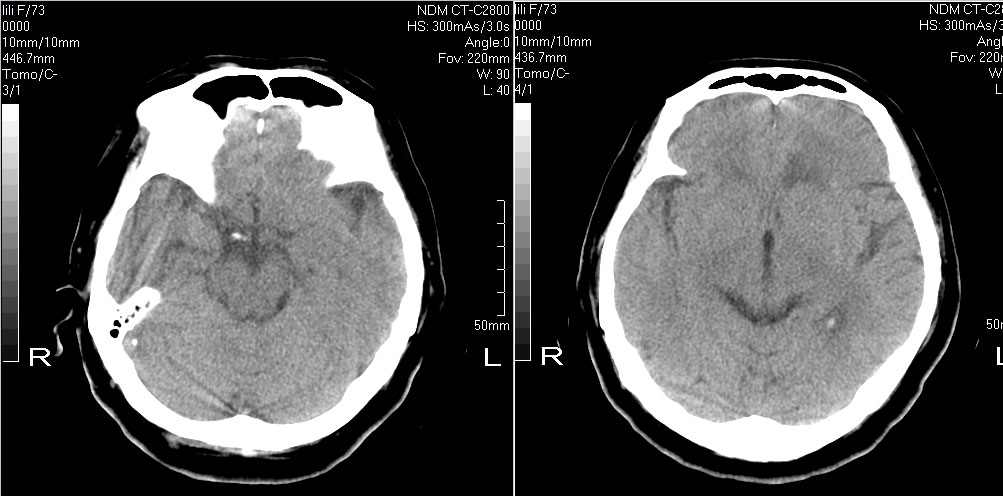

标题: CT10819:女,72,有高血压病史,突然寡言少语3日. [打印本页]

女,72,有高血压病史,突然寡言少语3日.

额叶多发梗塞,直回与人的情感有关

1左额叶梗塞(多有情感障碍)2皮层下动脉硬化症